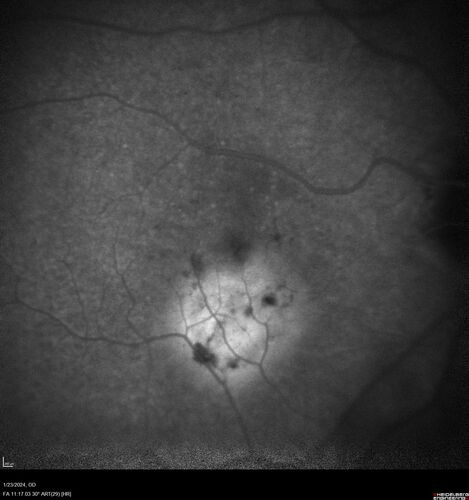

wet AMD with classic extrafoveal macular neovascularization in the good eye

89 year old man with longstanding vision loss in the left eye presented with one month of mild vision loss in the right eye.  Vision was 20/32.  This eye responded to vabysmo therapy.